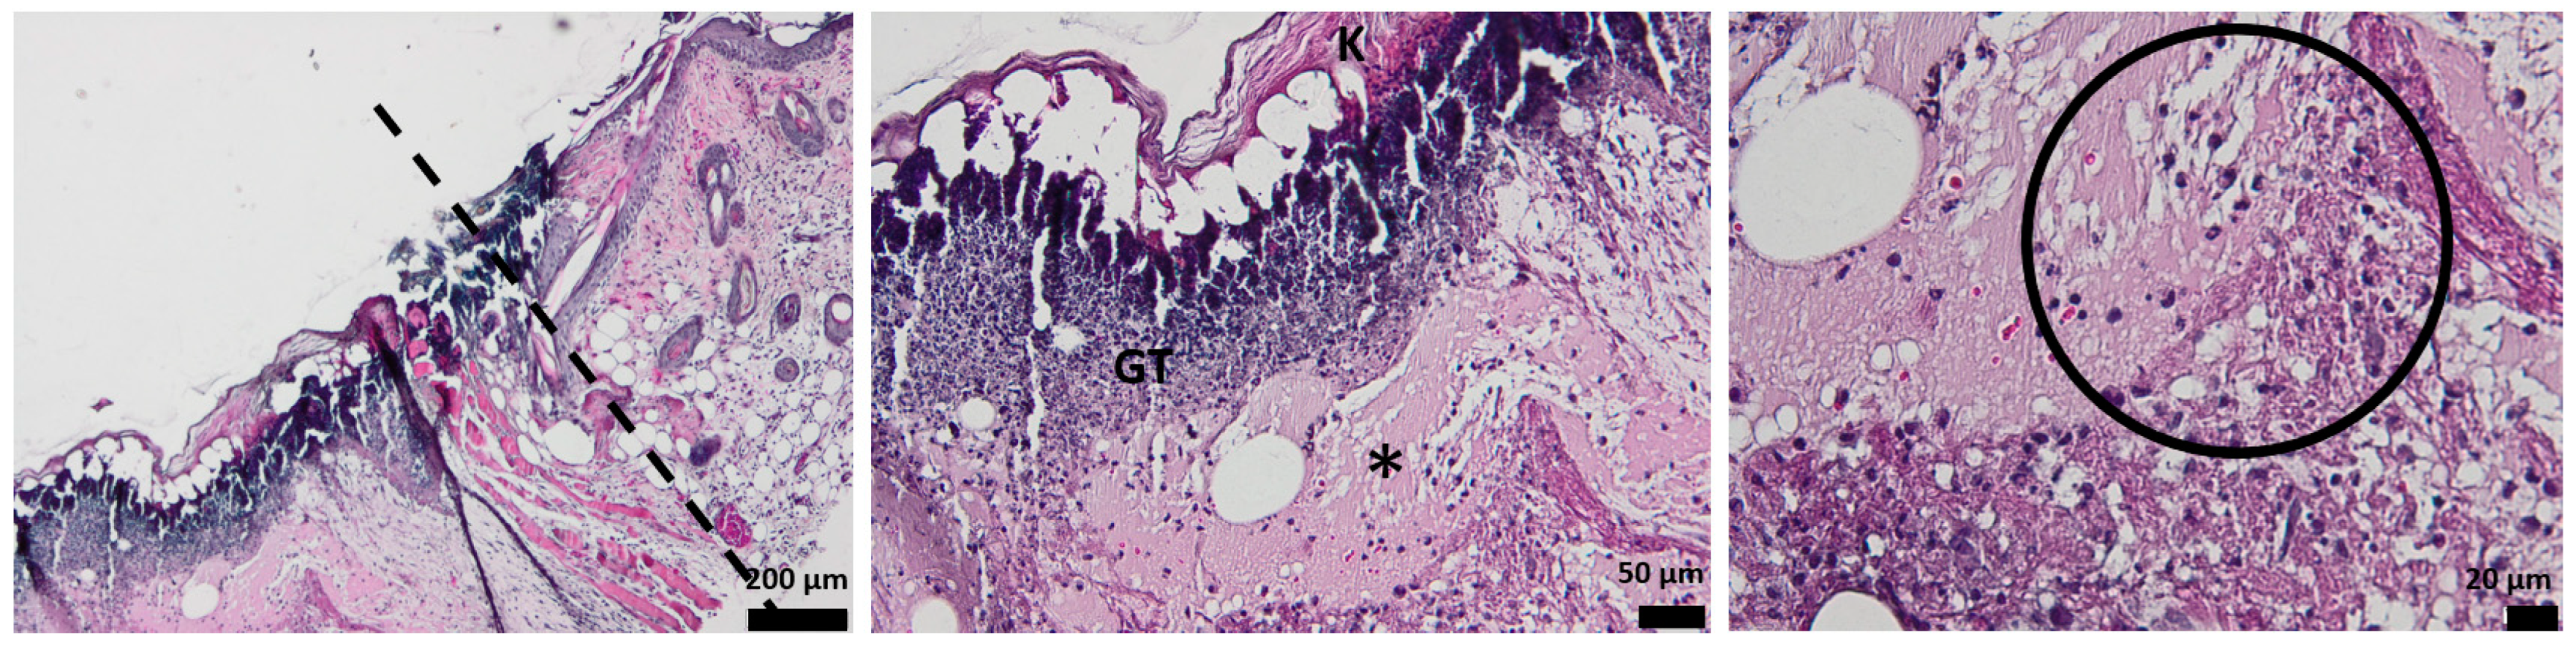

3.3. Histological Aspect of the Wounds 3 Days after Injury (H&E Stain)

3.4. Histological Aspect of the Wounds 7 Days after Injury (H&E Stain)